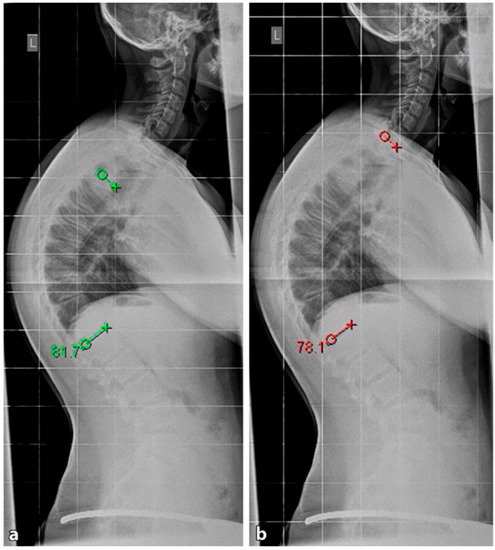

4.2. Diagnostics

Although initially described by Sorensen, the definition of SD has been definitively established by subsequent work by Edgren et al. and Blumenthal et al., with SD typically manifesting mostly in the thoracic spine (type I) and less commonly in the lumbar spine (type II) [79,85,86]; see Figure 7. The measurement of thoracic kyphosis according to Cobb (Th1–Th12) is sometimes difficult on conventional X-rays due to the humeral heads, so the Stagnara angle (Th4–Th12) is a reliable alternative (Figure 8). In children with SD, back pain and a positive family history are common, and clinical examination typically reveals a gibbus and a flexible deformity. In addition to a detailed medical history, a thorough physical examination is of utmost importance. The various signs and findings typical of SD are listed in Table 2.

4.2.1. X-ray

A standing anterior–posterior and lateral spinal radiograph is part of the standard imaging. Stereoradiographic imaging can be used alternatively to conventional radiography to create a three-dimensional reconstruction of a biplanar spinal X-ray with significantly less radiation exposure (EOS™) [31]. In addition to the representation of the kyphosis in the lateral view, these images also show the extent of curvature in the frontal plane according to Cobb, the curvature pattern, the sagittal profile or sagittal balance, and the apical vertebra. An assessment of spinal flexibility can be made using a clinical examination or a hyperextension lateral radiograph. The various features can be observed in radiological diagnostics, as shown in Figure 7. In up to 50% of cases, scoliosis and spondylolysis are accompanying pathologies [87,88].

4.2.2. Magnetic Resonance Imaging

The need for MRI diagnosis has been demonstrated in several studies. In a recent study, the prevalence of syringomyelia was found to be 5.8% in patients with SD [89]. MRI is an obligatory preoperative preparation to exclude myelon compression, thoracic disc herniation, or spinal canal stenosis. Figure 9 provides a comparative visualization of thoracic SD captured through different imaging techniques: stereoradiography, MRI, and computer tomography (CT).